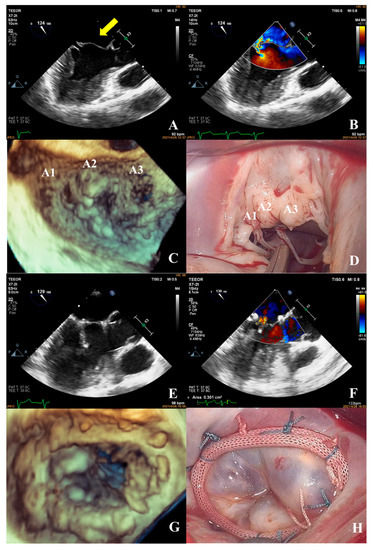

Prediction of Surgical Approach in Mitral Valve Disease by XGBoost Algorithm Based on Echocardiographic Features

In this study, we aimed to develop a prediction model to assist surgeons in choosing an appropriate surgical approach for mitral valve disease patients. We retrospectively analyzed a total of 143 patients who underwent surgery for mitral valve disease. The XGBoost algorithm was [...] Read more.

In this study, we aimed to develop a prediction model to assist surgeons in choosing an appropriate surgical approach for mitral valve disease patients. We retrospectively analyzed a total of 143 patients who underwent surgery for mitral valve disease. The XGBoost algorithm was used to establish a predictive model to decide a surgical approach (mitral valve repair or replacement) based on the echocardiographic features of the mitral valve apparatus, such as leaflets, the annulus, and sub-valvular structures. The results showed that the accuracy of the predictive model was 81.09% in predicting the appropriate surgical approach based on the patient’s preoperative echocardiography. The result of the predictive model was superior to the traditional complexity score (81.09% vs. 75%). Additionally, the predictive model showed that the three main factors affecting the choice of surgical approach were leaflet restriction, calcification of the leaflet, and perforation or cleft of the leaflet. We developed a novel predictive model using the XGBoost algorithm based on echocardiographic features to assist surgeons in choosing an appropriate surgical approach for patients with mitral valve disease. Full article